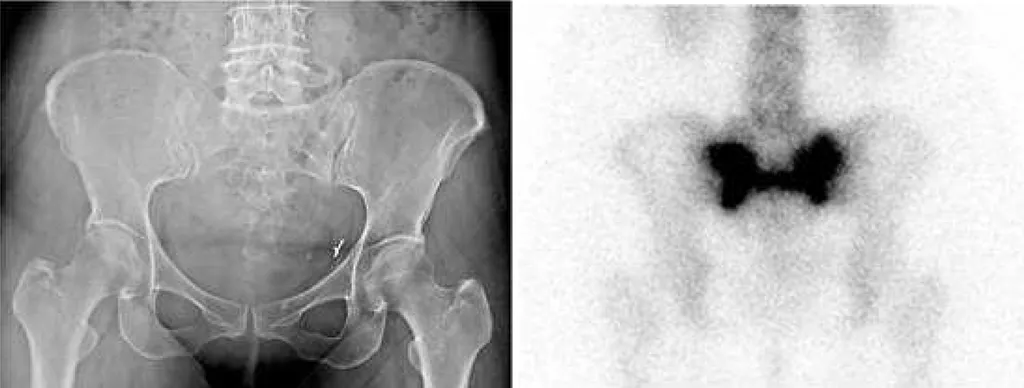

【109-1 醫學(五) 第72題】58歲女性已切除子宮及卵巢,另患有骨盆腔惡性肉瘤,並接受手術及放射治療,主訴最近下背痛,X光及核醫骨掃描如附圖,最可能的診斷為何?

這題的解題核心在於辨識核醫骨掃描(bone scan)中,薦骨(sacrum)出現的經典「H」字型高攝取影像,結合病患曾接受骨盆腔放射治療的病史,最符合薦骨不全性骨折(sacral insufficiency fracture)的診斷。